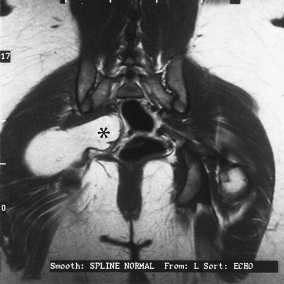

La resonancia magnética es la técnica de elección para definir la anatomía de los tumores del tejido blando. En base a los signos características, varias lesiones --los lipomas, hemangiomas, y gangliones-- puede diagnosticarse con precisión con un grado alto y fiable de especificidad.

Los lipomas tienen signos característicos que son exactamente idénticas a la grasa hipodérmica en todas las secuencias. Puede haber áreas pequeñas de cordones fibrosos. Los lipomas se demarcan bien y no invaden o penetran los límites de la fascia. No tienen el modelo de crecimiento centrípeto de los sarcomas y a menudo forman apéndices o áreas irregularmente formadas en dónde comprimen los planos intermuscular  o el espacio adventicial (Figura 1A y 1B).